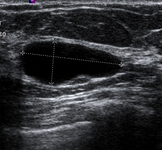

Imagem ultrassonográfica de um cisto simples

Cortesia do Dr. Lane Roland, Universidade de Louisville; usado com permissão